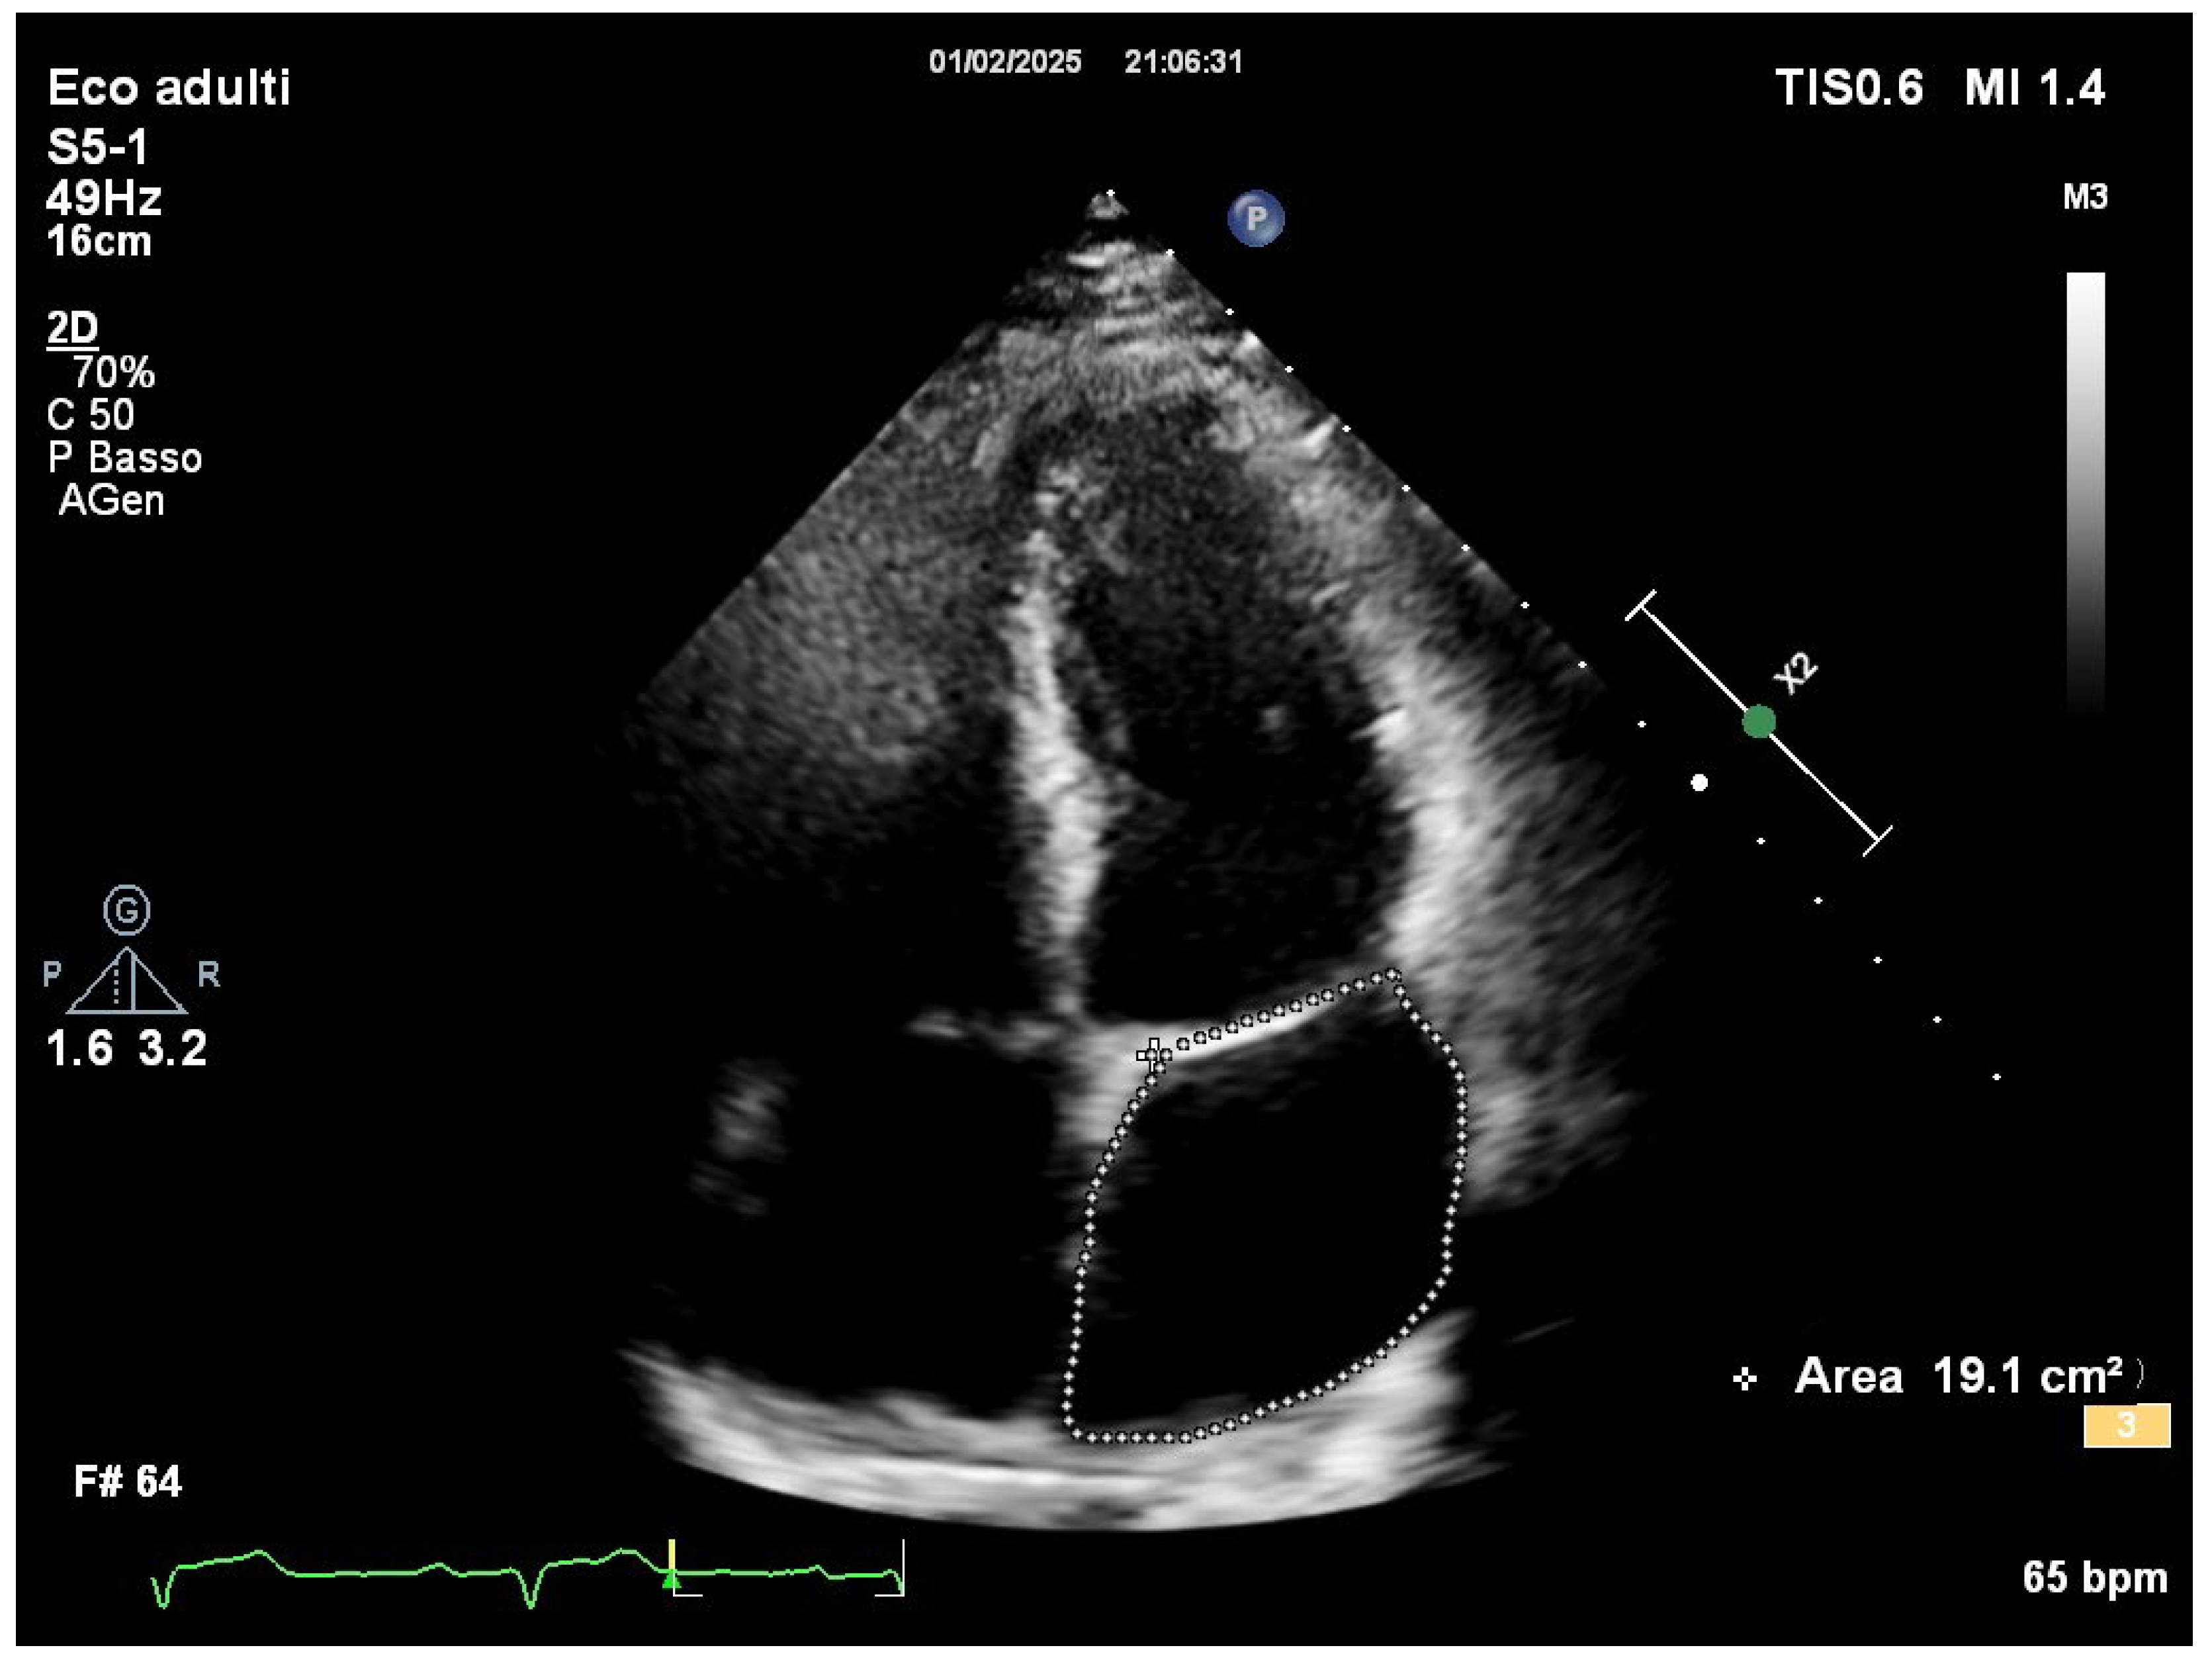

Comprehensive transthoracic echocardiographic evaluation revealed a normal left atrial volume, with no evidence of dilation and a left atrial volume of 19.1 cm2 (Figure 2).

Figure 2. Left atrial area measured in apical 4-chambers view.